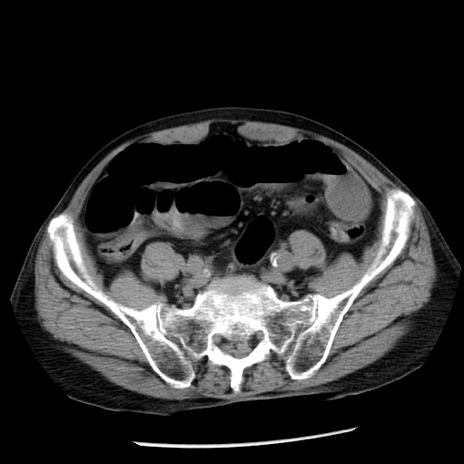

冠状断像

症例26(横断像)

【症例】80歳代男性

【主訴】嘔吐

【現病歴】昨晩2回嘔吐あり、今朝になっても嘔吐あり。来院。

【既往歴】胃潰瘍

【身体所見】意識清明、BT 37.6℃、BP 166/95mmHg、HR 100bpm、SpO2 97%、腹部:平坦・軟、腸蠕動音聴取良好、圧痛なし。

【データ】WBC 21900、CRP 1.46